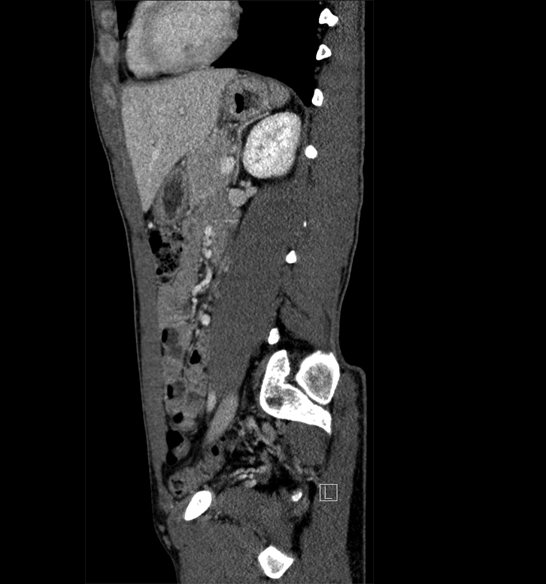

Body

Covers abdominal CT anatomy.